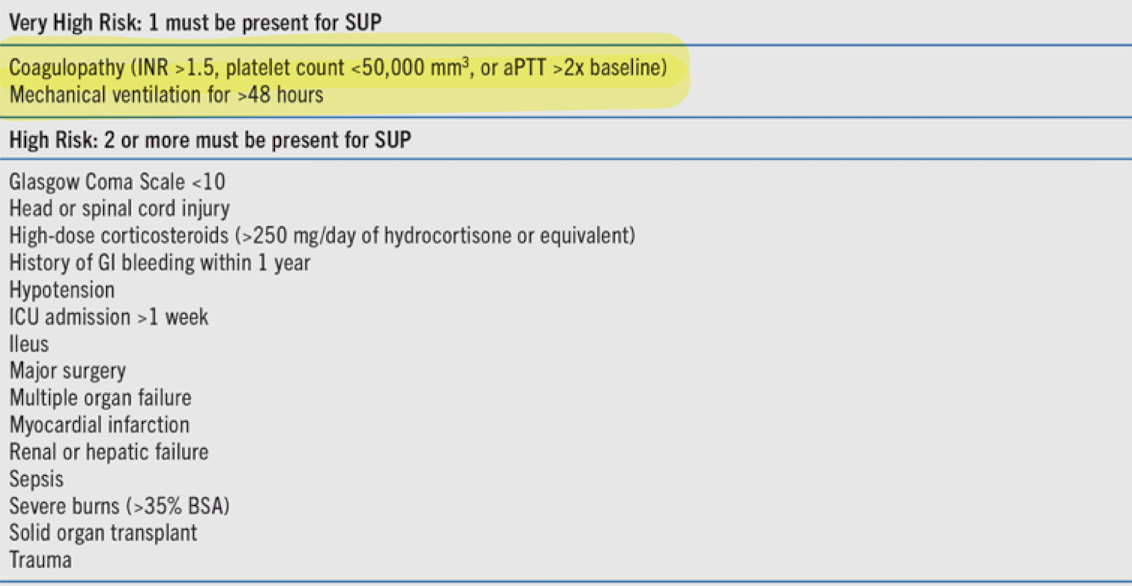

Pantoprazole (PPI)

gastric stress ulcer formed due to impaired mucosal protection and hypersecretion of acid

-consider in patients with 1 major (coagulopathy, mechanical ventilation >48hr) or 2 minor risk factors

Prophylaxis: ________ (first line); H2 Blockers (Famotidine), Sucralfate

FASTHUGSBID- Ulcer prophylaxis